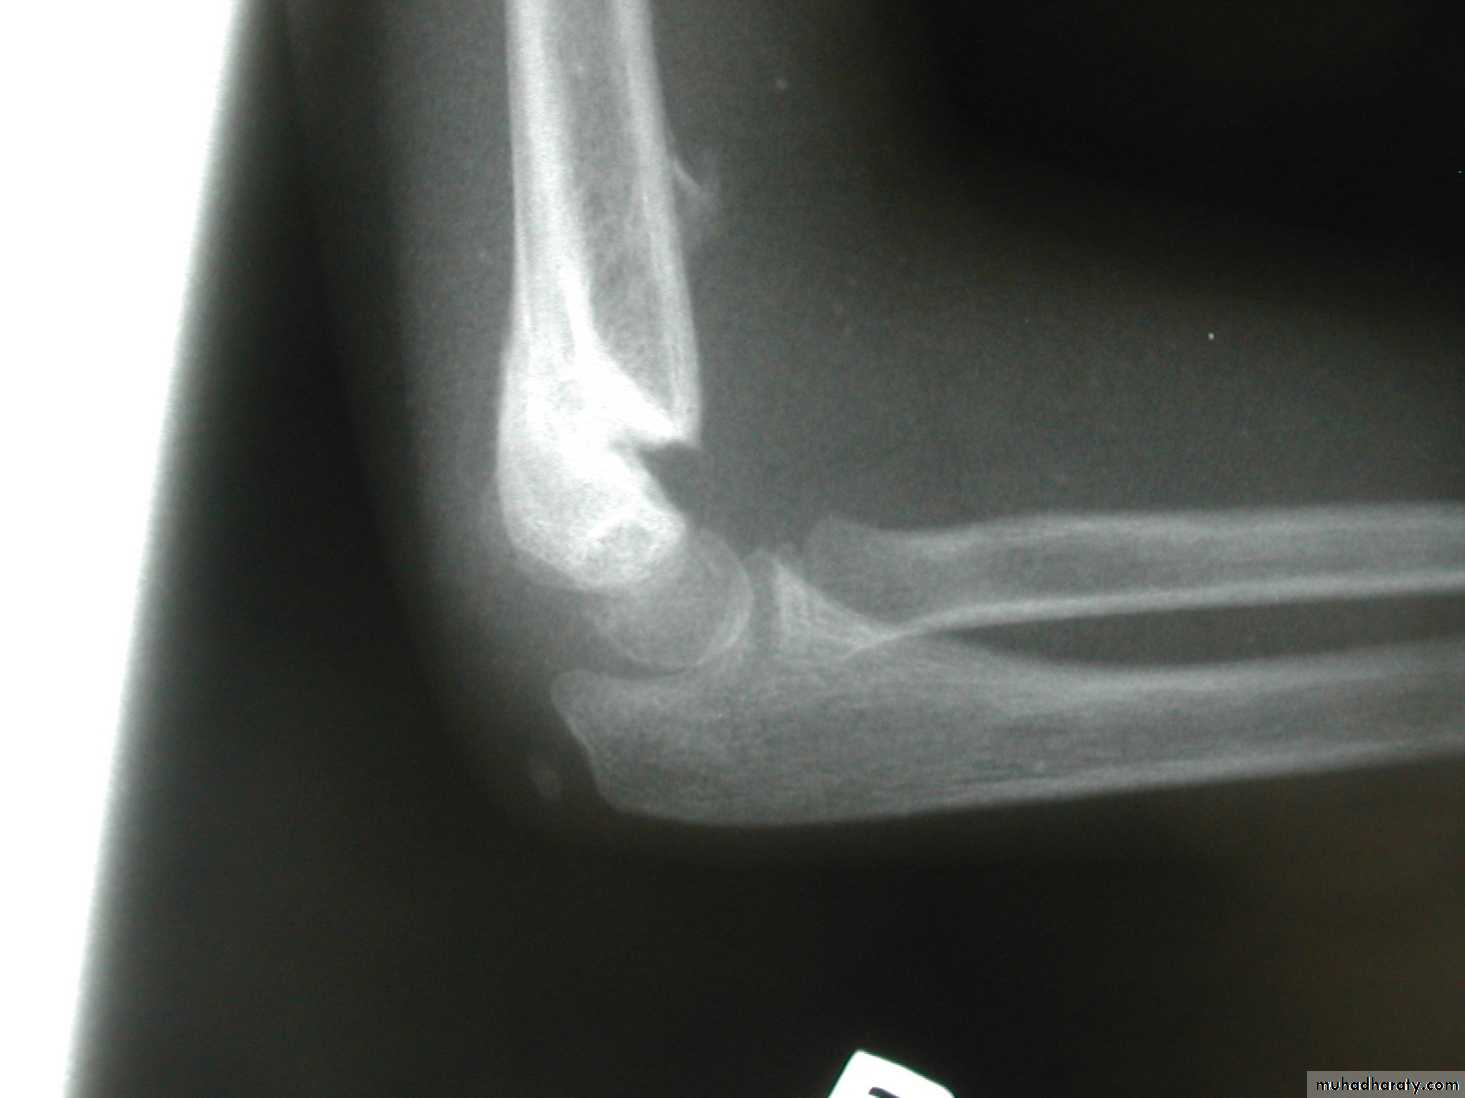

8 y.o.

Is this a simple extension

type supracondylar fracture ??

It also has

anterolatateraldisplacement !!

The distal fragment is

not flexed,but also it is not extended to any degree.

This also is a Type III Flexion Pattern.

What is differentabout this fracture?

But, if not recognized as such, it may be a problem.

This fracture was irreducible,

and required an open reduction !!!